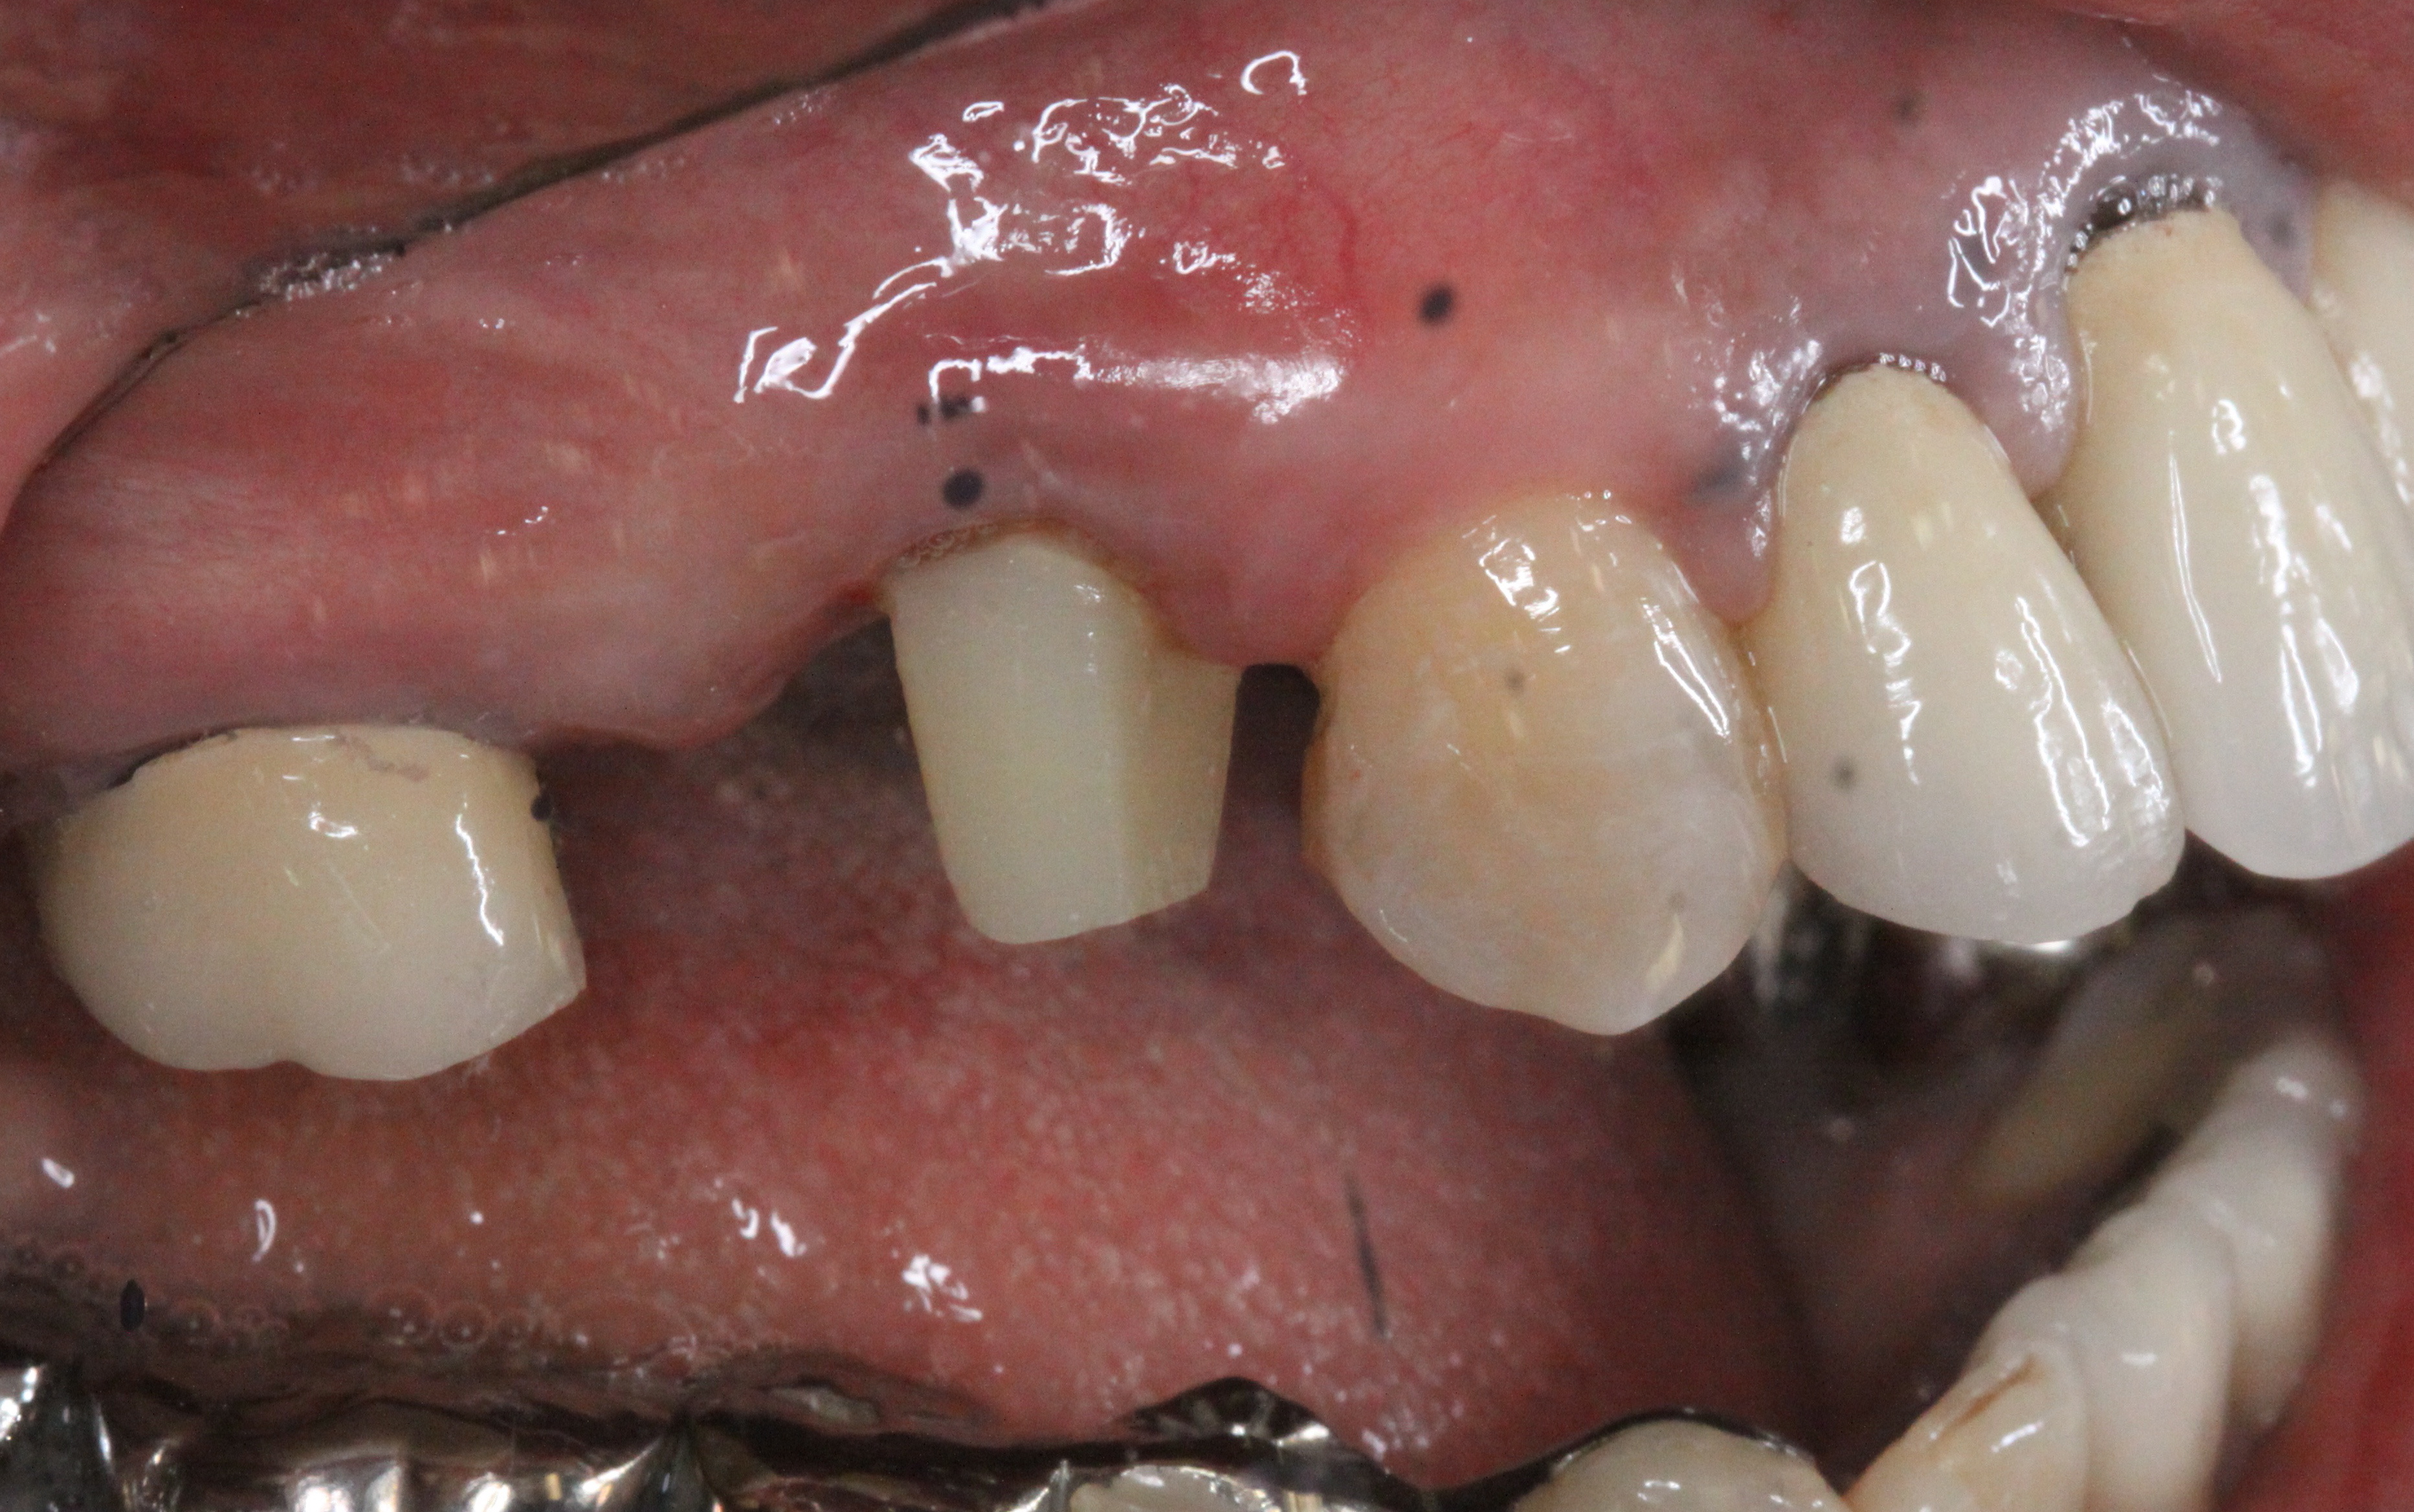

修復後

きれいにした後に、修復をして元に戻しました。

再植後

治療前